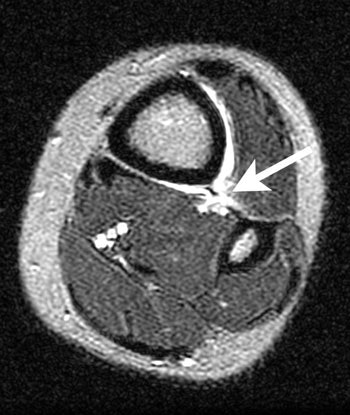

| Axial FSEIR at the tibial plafond shows rupture of the anterior and posterior tibiofibular ligaments, and the interosseous membrane (arrow). |